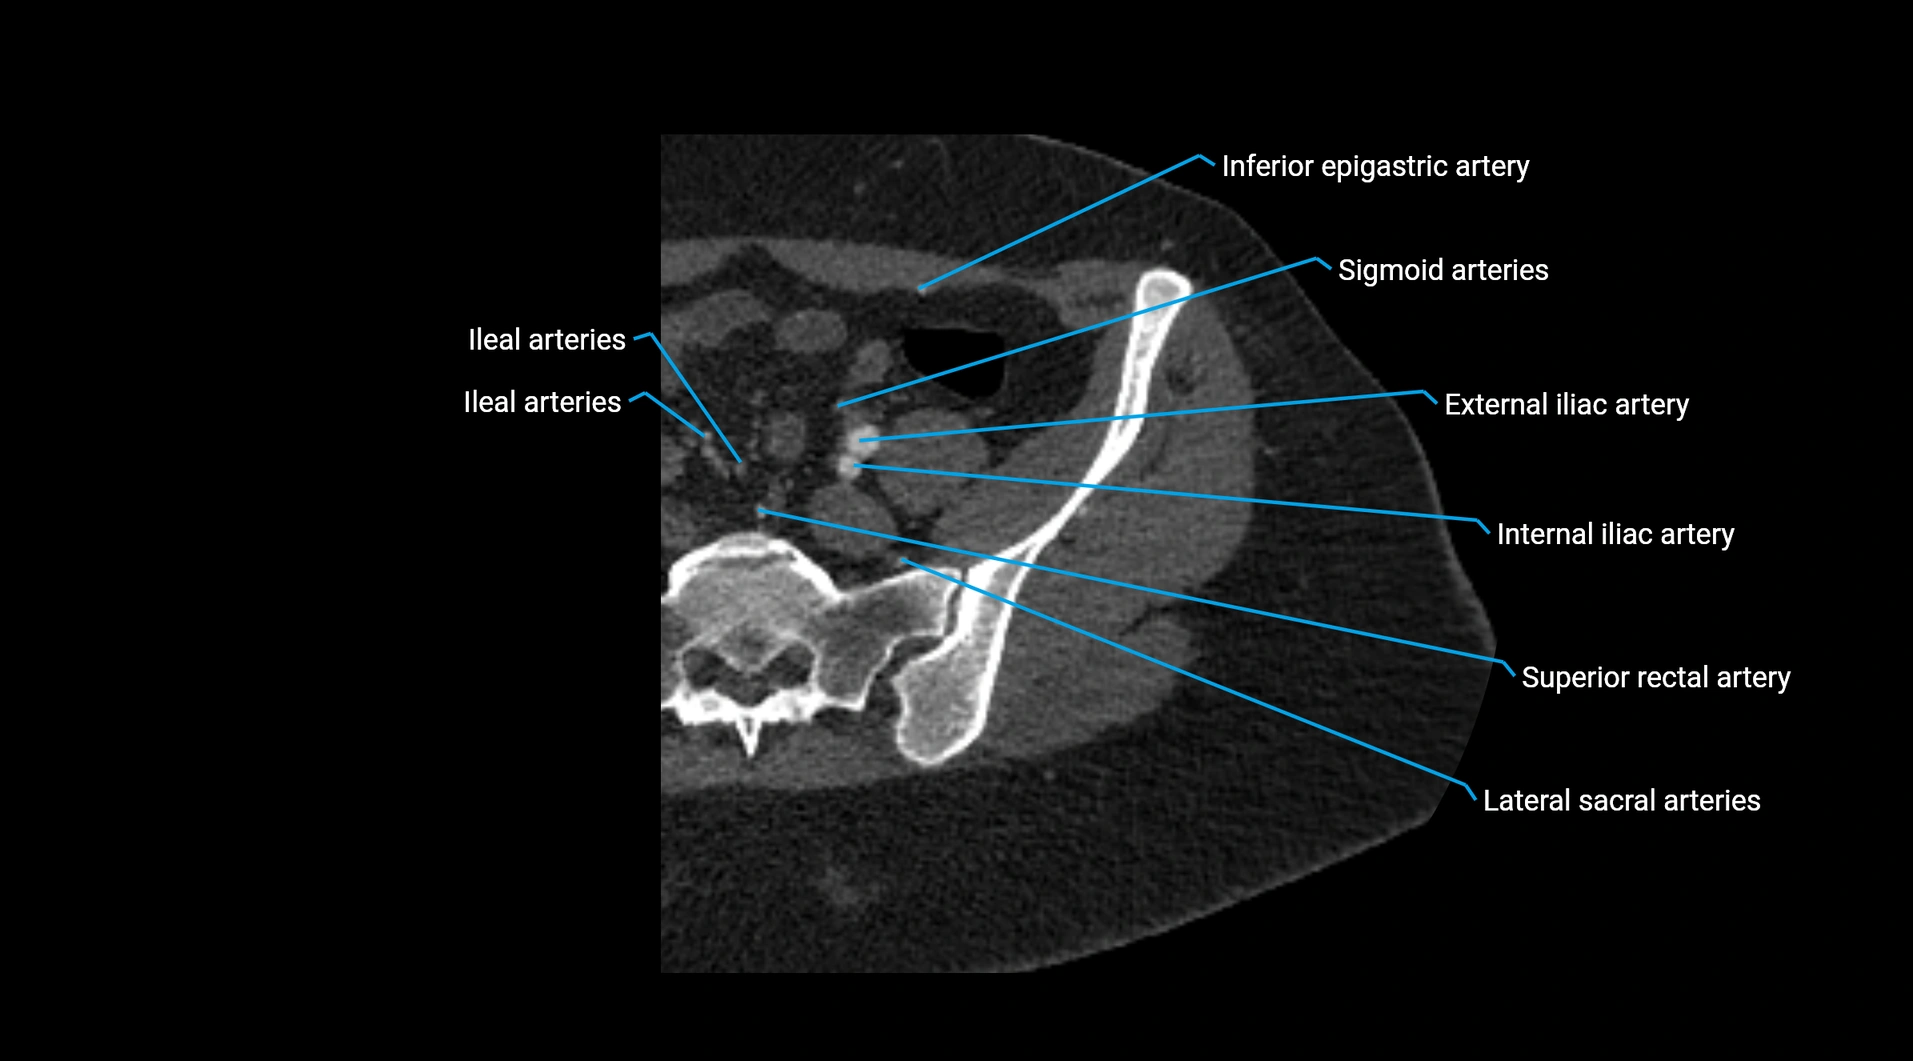

CT images

image

Contrast-enhanced CT (CTA):

• Gold standard for abdominal aortic imaging

• Provides excellent detail of lumen, wall, aneurysm, thrombus, and branch vessels

• Multiplanar and 3D reconstructions help in aneurysm measurement, stent graft planning, and dissection evaluation